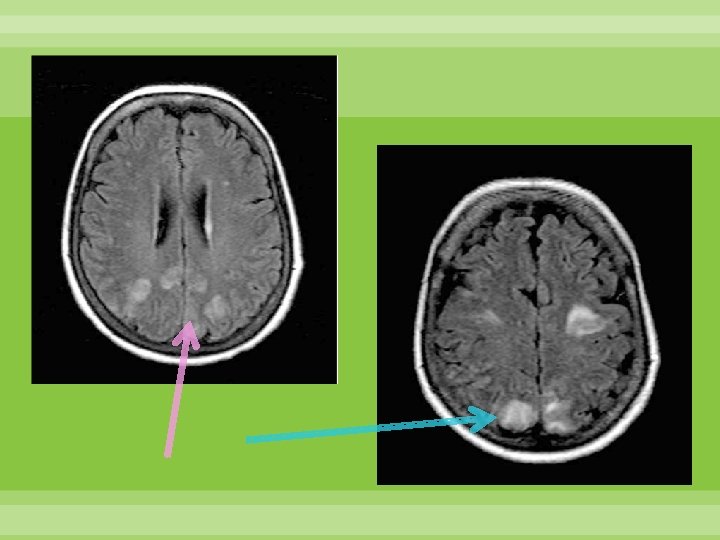

Leucoencefalopatía posterior reversible Secundario a vasoconstricción sostenida Disminución de inervación simpática en la circulación posterior. Reversible Cefalea súbita, pérdida de la visión, náusea, vómito, alteración del estado de alerta Secuelas asociadas a infarto o hemorragia Schwedt, Matharu, Dodick Thunderclap headache Lancet Neurol 2006; 5: 621– 31

Edema vasogénico en sustancia blanca posterior: parietal y occipital, puede extenderse a ganglios basales, tallo y cerebelo Schwedt, Matharu, Dodick Thunderclap headache Lancet Neurol 2006; 5: 621– 31